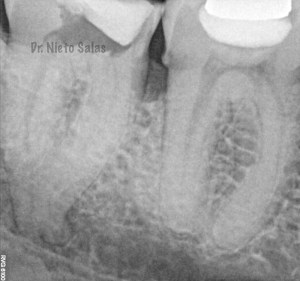

2. disculpe, en las imagenes de la entrada de los conductos, era dos conductos distales o era solo uno ?? muchas gracias y enhorabuena por el casa, es perfecto !!

3. Dr Nieto Salas, en la imagen en que se ven la camara con la entrada de los conductos y la gutapercha, el orificio de entrada en distal era muy ancho, a parte de conductos laterales, localizo un conducto o dos conductos ?? ( la duda es por lo ancho de la entrada). El caso es maravilloso. Le doy mi enhorabuena.

4. Hola Juan,

en ese caso en particular, el número de conductos era solamente uno, ya sabes que los conducto distales en muchas ocasiones tienen forma ovalada, con lo que la entrada puede corresponder con las imágenes.